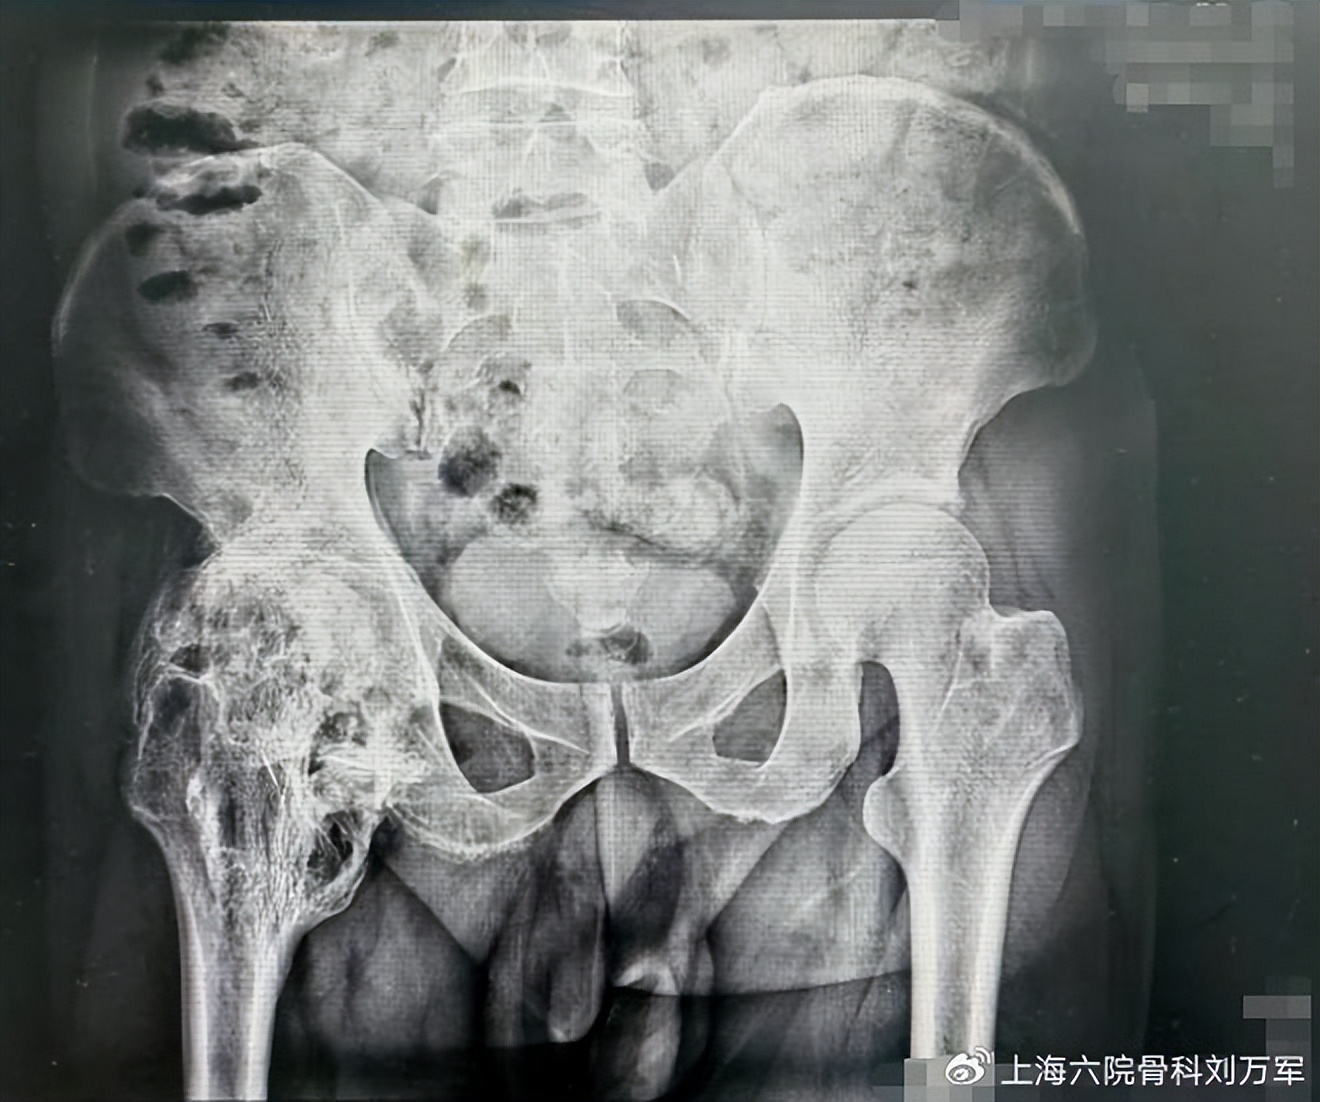

闫先生因为两年前的一次车祸造成的损伤,在西安的某医院做了右髋关节内固定术。尽管手术成功,但术后还是带来了令他无比痛苦的后遗症——异 位骨化。 闫先生的右髋关节出现持续疼痛伴骨质增生,关节僵硬,屈曲受限。走路时变得跛脚,连最最日常的穿脱鞋袜,对他来说也成了一项挑战。异 位骨化是指正常情况下在无骨组织的软组织内形成新生骨。它多发生于骨折、关节置换术、脊髓损伤、脑损伤等之后,好发于髋、肘和膝关节周围。闫 先生正是如此,他的异位骨化就发生在做过手术的右髋关节部位。对于异位骨化严重影响关节功能者,手术切除是目前唯一的治疗手段。然而,闫先生的情况却相当棘手——右髋关节处的骨质“疯长”导致新生的骨质把关节包裹得像树根一样。过去的两年时间,他和家人们走遍全国各地的医院,均未得到根本的救治。

抱着最后一丝希望,闫先生和家人慕名来到了上海市第六人民医院临港院区。关节外科的刘万军主任医师带领团队为他检查治疗。在对闫先生的病情进行了全面评估后,刘万军主任医师和团队医务人员发现闫先生的髋关节出现了360度异位骨化。 也就是说,右髋关节的前后上下都被增生的骨质包围,就像一个正常的髋关节被“全部焊死”,完全不能动弹。 对于异位骨化切除手术而言,选择合适的手术入路,术中尽量减少对骨膜、骨质、关节囊和周围组织的损伤是十分重要的。然而,闫先生髋关节的骨化和周围的神经、血管贴得很近,前方有股神经和股动脉,后方有坐骨神经,术中稍有不慎,就可能造成不可逆的损伤,甚至危及性命。总的来说,这场手术面临着非常高的风险。